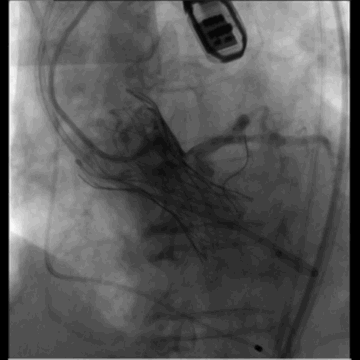

冠脉遮挡,LM植入支架

冠脉灌注良好,确认人工瓣膜位置

左髂动脉“翻山造影”下缓慢退鞘,造影观察无血管损伤,手术结束。

退鞘

外周血管造影